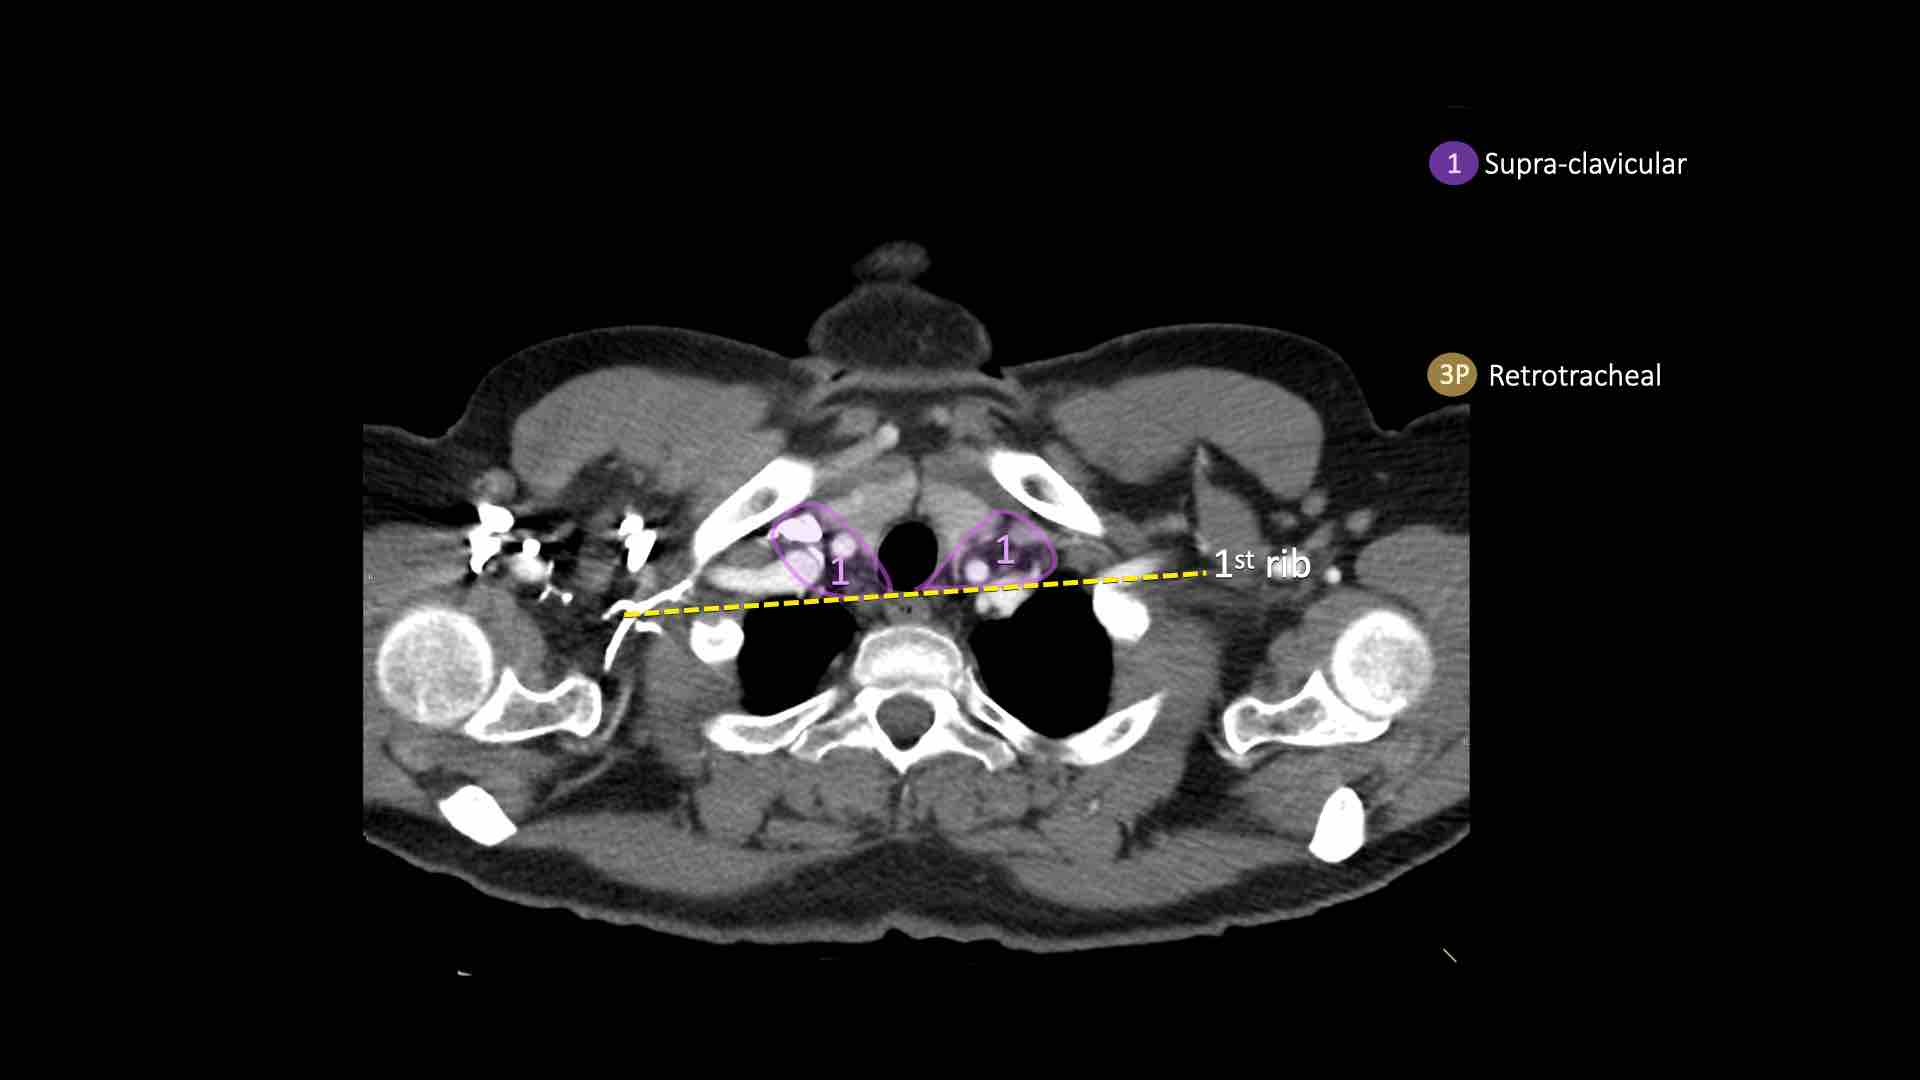

3P.Trước cột sống

Các hạch không tiếp giáp với khí quản như các hạch ở nhóm 2, mà nằm sau thực quản, tức là ở vị trí trước cột sống.

1. Hạch vùng thượng đòn

Bao gồm các hạch cổ thấp, thượng đòn và hạch khuyết ức.

Ranh giới trên: bờ dưới sụn nhẫn.

Ranh giới dưới: xương đòn và bờ trên cán ức.

Đường giữa khí quản là ranh giới phân chia giữa nhóm 1R và 1L.